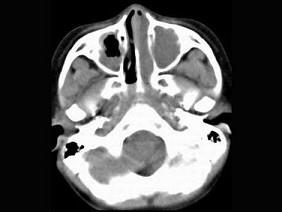

问题 男,7岁,无意发现鼻腔肿物,无明显症状,CT如图所示,最可能诊断为 ( )

选项 A、鼻乳头状瘤 B、鼻炎及副鼻窦粘膜下囊肿 C、鼻炎 D、鼻炎鼻息肉 E、鼻淋巴瘤

答案 D